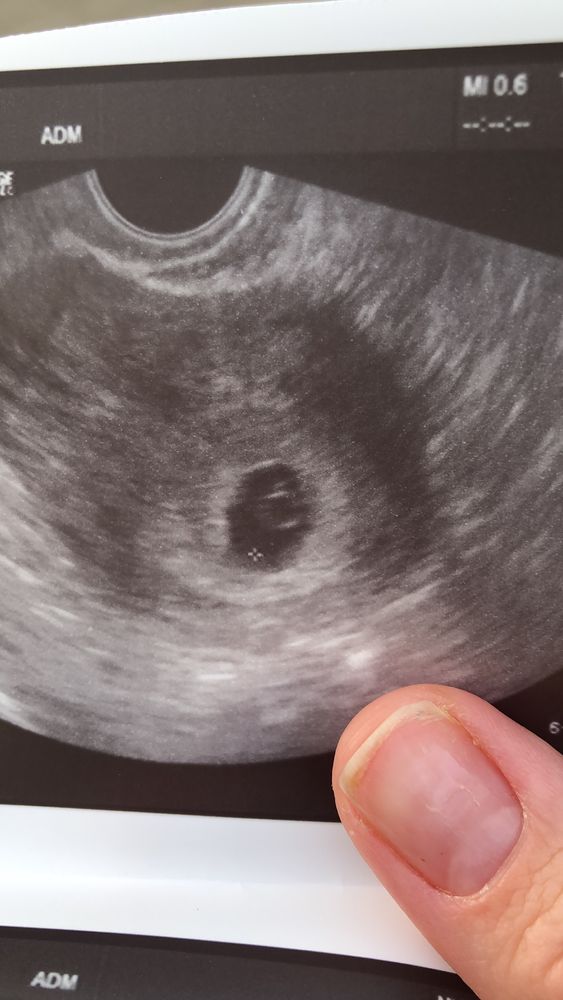

Хгч стал падать и вчера на первом УЗИ в 6.2нед увидели ПЯ в матке пустое и по размеру менее 3мм